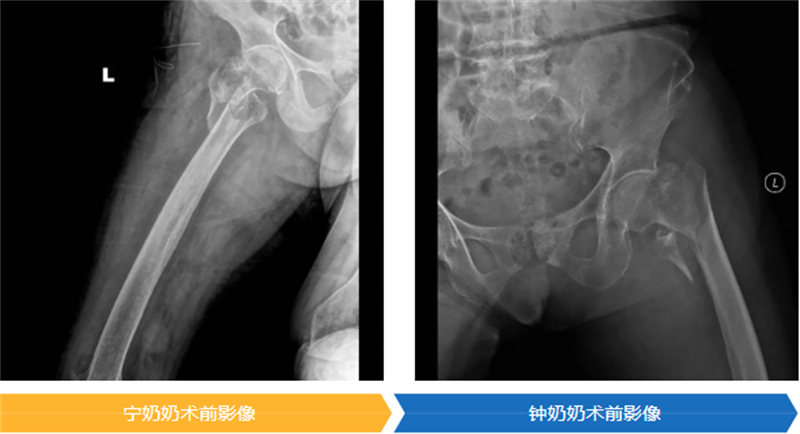

手術是讓老人重獲生機的關鍵一步,但同時也是對百歲高齡軀體的嚴峻挑戰。為了以最小的創傷換取最大的生存機會,醫療團隊為兩位老人精心選擇了“股骨近端防旋髓內釘(PFNA)”這一微創固定方案。

時間就是生命。在醫院為高齡患者開通的綠色通道保障下,兩位老人均在入院24小時內接受了這關鍵性手術,并順利完成。隨后,在重癥監護室(ICU)團隊的晝夜精心守護下,兩位百歲老人平穩渡過了術后最危險的階段,為后續的康復贏得了寶貴的時機。

在大家溫暖的鼓勵和專業的幫助下,寧奶奶在手術后第三天,就穩穩地站起來了;鐘奶奶也在第五天,堅強地扶著助行器邁開了步子。能早點下床,就意味著能把肺炎、血栓這些“臥床病”遠遠推開,恢復得更順利,也能早一點回家。